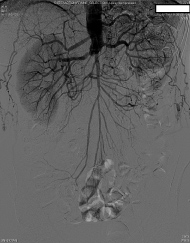

Preoperatively, the surgery service was queried by the anesthesiologist as to whether the routes of collateralization to the lower extremities were known. The response indicated that there had been intraabdominal collaterals demonstrated on angiography from the radial artery catheterization upon admission. The patient was then transported to the operating room, and a radial arterial line was placed during preoxygenation and prior to induction. After further consideration, the surgeon requested a delay of induction of anesthesia for further angiography review. Upon examination, a large right inferior epigastric artery was noted on the preoperative catheterization films, suggesting that collateral blood from the right internal mammary artery may supply the right lower extremity. The origin of collateral flow, however, could not be determined. Existing angiography was also unable to clearly demonstrate the collateral blood flow to the left lower extremity. At this point, the case was aborted before induction of anesthesia, and further angiography studies were ordered in consultation with a vascular surgeon. A subsequent aortogram and angiography of the internal mammary arteries demonstrated that collateral flow to the lower extremities was dependent on both the left and right internal mammary arteries (Figure 1, Figure 2 and Figure 3). Gastroepiploic artery was not considered as an alternative to the LIMA because of lack of institutional experience with the procedure.

Figure 1: Angiogram demonstrating infrarenal aortic occlusion with collateralization.